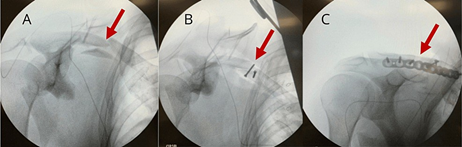

Figure 2 Intra-operative X-Ray images of the right clavicle highlighting

A) Displaced fracture of mid-portion of clavicle,

B) Fracture reduction,

C) Fracture internal fixation.